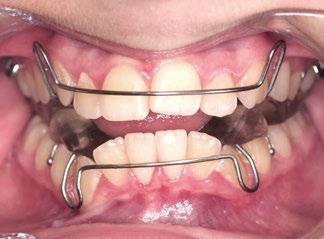

En este artículo se describe el caso de una niña de 9/2 años con síndrome de Clase II por hipoplasia mandibular que recibió tratamiento en dos fases: una primera, ortopédica, para estimular el crecimiento mandibular mediante aparatología funcional; y una segunda fase, ortodóncica, con la colocación de brackets de autoligado pasivo de la técnica USS (Universal Smile System) de prescripción variable para el desarrollo y coordinación de las arcadas dentarias.

El diagnóstico reveló una Clase II ósea y dentaria, con hipoplasia mandibular, estando indicada la colocación de un aparato funcional por los motivos detallados más adelante.

El aparato funcional con el que se realizó el primer avance mandibular fue un Bionator (3-5), que consta de dos cuerpos de acrílico, superior e inferior, adaptados a las arcadas dentarias y unidos en un solo bloque mediante la mordida constructiva. En el sector anterior el acrílico se extiende hasta el 1/3 incisal por vestibular para evitar la disminución del resalte por la protrusión de los incisivos inferiores. El arco vestibular continúa hacia los sectores laterales configurando las asas buccinatorias, que al disponerse separadas 1-2 mm del tejido dentario y gingival restringen el componente de fuerza externa de los músculos buccinatorios.

El segundo avance mandibular se realizó con un Twin Block (6,7), que consta de dos bloques de acrílico, uno en la arcada superior y otro en la inferior, que se solapan entre sí cuando el paciente ocluye, mediante unos planos inclinados de resina que provocan el avance mandibular y transmiten fuerzas favorables a los planos inclinados oclusales que cubren a los dientes posteriores.

Los planos inclinados forman un ángulo de 70 º con el plano oclusal; con esta inclinación, aun en posición de reposo, la mandíbula se mantiene en posición adelantada,

Figuras 1-3.

La niña de las figuras 1 a 3 presenta una leve asimetría facial con patrón braquifacial por tercio inferior disminuido y mentón desviado ligeramente hacia la derecha; los labios son competentes y en sonrisa apenas se exponen los incisivos. El perfil es excesivamente convexo,

La exploración intraoral (figuras 4 a 8) revela una Clase II molar y canina completa, líneas 1/2 dentarias superior 0,5 mm e inferior 1 mm ambas desviadas hacia la derecha, los incisivos superiores excesivamente protruidos y vestibulizados (seguramente debido a la interposición del labio inferior), resalte de 13 mm y sobremordida 2/3 de corona. La discrepancia oseodentaria

inferior es de -3,5 mm y la curva de Spee de 4 mm.